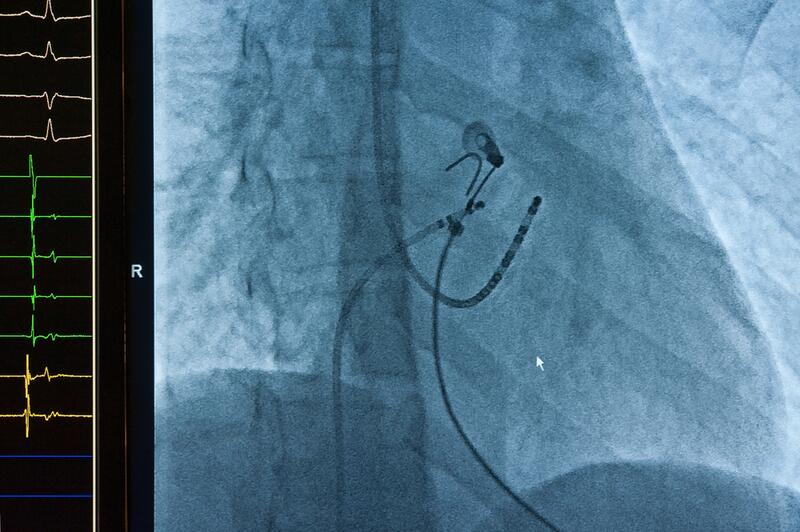

Пейсмейкерами (искусственными водителями ритма/кардиостимуляторами)лечатся блокады- нарушения проведения импульсов в проводящей системе сердца и синдром слабости синусового узла- при котором сердце не способно само вырабатывать управляющие импульсы.

Существуют еще пейсмейкеры-дефибрилляторы.

Они отслеживают приступы фибрилляции (трепетания) не предсердий, а желудочков сердца, и довольно мощным электрическим импульсом обрывают его, восстанавливая нормальные сокращения и предотвращая внезапную смерть, например в случае приступа Морганьи-Эдемс-Стокса.